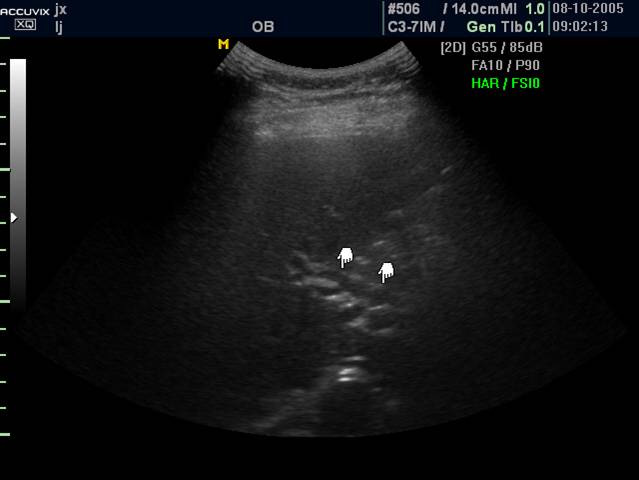

4 胆道蛔虫病